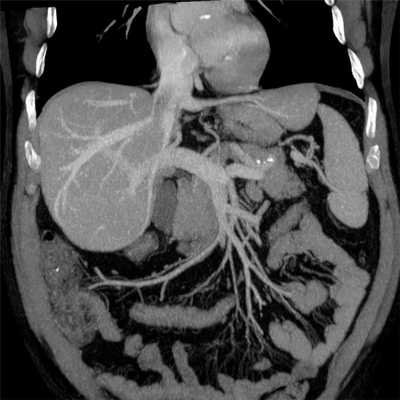

Radiology department of the Rijnland Hospital Leiderdorp and the University Medical Centre Groningen, the Netherlands.КТ-ангиография сосудов брюшной полости

![КТ-ангиография сосудов брюшной полости]()

КТ-ангиография сосудов брюшной полости считается одним из наиболее современных методов определения состояния здоровья сосудистой системы в указанной области. Его главным отличием выступает привлечение специального контрастного вещества.

Обычное ультразвуковое исследование не способно предоставить развернутую картину по структуре и общему состоянию сосудов в брюшной области, что способствовало разработке и внедрению технологии ангиографии. Вместе с контрастом получается визуализировать абсолютно все участки сосудистого русла. На основе полученной визуализации доктор сможет определить не только строение больших и мелких сосудов, но также выявить возможные аномалии в близлежащих органах.

Детализированная картина помогает обнаружить даже малейшие просветы, либо выявить внутренние образования, будь то онкологические опухоли или обычные тромбы. Причем изображение настолько подробно, что опытный рентгенолог способен на его основе распознать только-только зарождающиеся заболевания. Особенно актуален поиск недугов на начальной стадии развития для онкологических заболеваний.